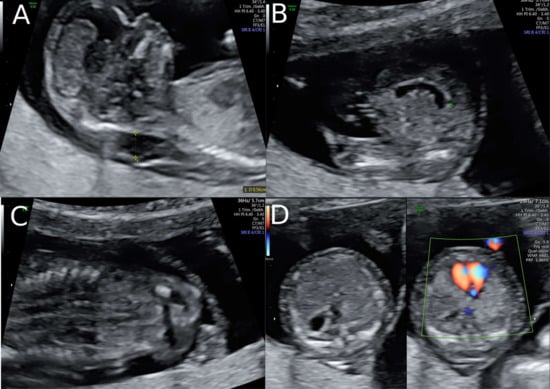

A 38-year-old women with a dichorionic-diamniotic twin pregnancy, after in-vitro fertilisation, attended routine first trimester screening at 13 + 4 weeks of gestation. One of the twins (fetus I) pair showed normal NT measurement and a low risk for chromosomal abnormalities, whereas the other twin (fetus II) presented an increased NT of 5.2 mm, the position of the fetal heart in the middle of the thorax, and hyperechogenic kidneys (Figure 1). At this stage, the patient declined invasive diagnosis. At 15 + 5 weeks of gestation, additional findings to the ones above, including hydronephrosis, skin oedema, and a right-sided clubfoot, have been observed. Subsequently, amniocentesis in the affected fetus was performed and revealed a 46, XY karyotype. Estimated fetal weight for both were average for the gestational age but abdominal circumference (AC) of the second twin was at the 95th percentile. At 22 + 0 weeks of gestation, the overall estimated fetal weight of fetus II was above the 95th percentile and a nuchal fold of 8.1 mm with general oedema of the skin was present. The ultrasound scan additionally showed a striking profile (Figure 2). All measurements (HC-AC-FL) were above the 95th percentile. A suspicion of left-sided diaphragmatic hernia as well as hyperechogenic kidneys, increased in size and polycystic appearance, and a hypoplasia of genitalia have been identified. Furthermore, the scan revealed a polyhydramnios (DIP 10 cm). Due to the polyhydramnios of fetus II, fetus I has been compromised in a similar process as twin-to-twin transfusion syndrome, although fetal development and amniotic fluid have been normal (Figure 3).

Figure 2. Ultrasound at 22 weeks of gestation (A,B) Striking profile and brain structure in fetus with Simpson-Golabi-Behmel syndrome. (C) Suspicion of congenital diaphragmatic hernia at 22 weeks of gestation and (D) increased subcutaneous fat tissue.